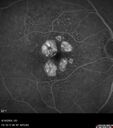

Most viewed - Occult CNVM wet AMD and Geographic Atrophy

77 year old female HPI: CC: Decreased Vision OU. Since Last Visit: worsening. Location: central vision. Context nset/Aggravation: while reading. Modifying Factors: when closes one of her eyes notices letters are missing. Duration of Problem: couple of months. Associated Symptoms: foggy circle temporal when driving OU. Severity: moderate. Course: intermittent . HPI obtained by Steven M. Cohen, MD, FACS Medical Hx: Hypertension, Systemic. Hyperlipidemia. Depression. Spinal Stenosis. Psoriasis. Osteopenia Systemic Meds: TIZANIDINE HCL. TRAMADOL HCL prn. ZOLPIDEM. HYDROCORTISONE. TRAZODONE HCL, Clobex 0.05 % Topical Spray. VA OD 20/32, OS 20/20 IOP 13 OU

Wet AMD - Occult CNVM and Geographic atrophy111 views77 year old female with mild vision loss - 20/32 - responded to Avastin